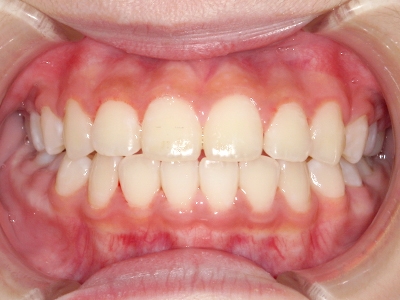

歯並びの相談に来られるお子様は、口呼吸をしているケースが多く、これが歯並びに大きな影響を与えています。

- 口呼吸をしている

↓ - 舌の位置が悪くなる

↓ - 頬の圧力が上の歯列にかかりやすくなる

↓ - 上あごが狭くなる

↓ - 下あごが狭くなる・下あごの位置が悪くなる

↓ - さまざまな不正咬合が生じる

ないき歯科クリニックでは、上あごの成長不足を補い、鼻呼吸を獲得しつつ歯列を整え、将来のお口をより健康な状態にすることをゴールに定める矯正治療をおこなっています。